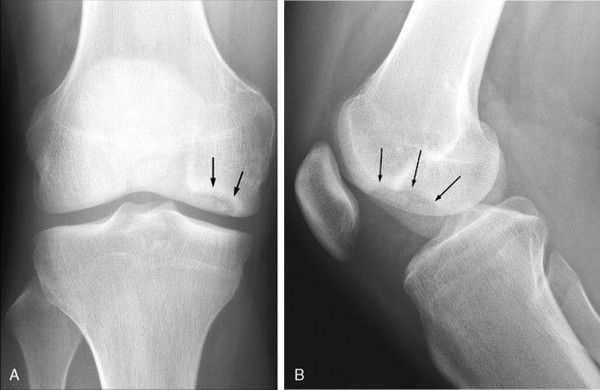

Клинически и рентгенологически в течении болезни Кенига различают две стадии. Первая стадия протекает обычно скрыто, без видимых проявлений, по типу неясного артрита без рентгенологических проявлений. Местно возникает отечность коленного сустава, боли неясной локализации. Только при диспансерном наблюдении за больным и периодическом рентгеновском контроле можно видеть в медиальном мыщелке бедренной кости появление поверхностно расположенного очага просветления. Очаг разрушения имеет ровные контуры. Постепенно этот очаг отторгается в виде свободно лежащего тела.

В дальнейшем эта стадия прерывается незначительной травмой и происходит выпадение свободного тела и ущемление его в суставе. Для второй стадии болезни Кенига характерны резкие боли в суставе, блокады сустава. Жидкость в суставе определяется редко, что отличает ее от блокады сустава при ущемлении поврежденного мениска. Рентгенологически во второй стадии ниша бывает пустой, а выпавшее тело из медиального мыщелка бедренной кости обнаруживается в полости коленого сустава.

Инструментальная диагностика начинается с рентгенографии сустава в прямой и боковой проекциях, а также в специальных укладках — рентгенография в заднепередней проекции при сгибании в колене до 45 ° и аксиальная (осевая) рентгенограмма надколеннико-бедренного сустава. Рекомендуется проводить рентгенографию обоих коленных суставов, если даже признаки нарушения наблюдаются только в одном, так как в практике около 25 % случаев приходится на билатеральное поражения суставов.